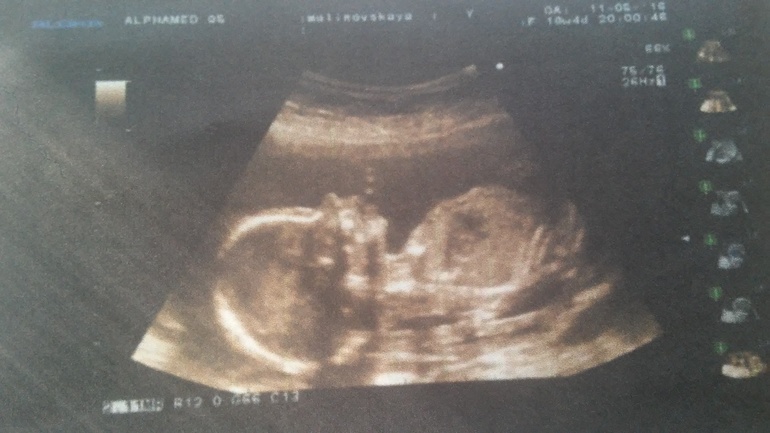

Вчера ходили с мужем на 4 д узи, нам уже 19 недель! Хотели узнать точно пол ребеночка, в 13 недель ставили девочку, а тут показали наше хозяйство- у нас мальчик!!! Были немного приятно шокированы! Мы уже весим 300 гр. У малыша всё хорошо, а у мамы +3 кг.)))) Роды ставят не позже 8 октября!))

Очень удачное фото))) губки пухлые и носик чёткий))) голова маленькая ещё)) я тоже УЗИ на 19-20 нед делала (на микимауса похож) и на 23-24 нед (за месяц так голова выросла, руки в кулочках и профиль чёткий, человеческий))) вот фото моего малыша в 20/24: